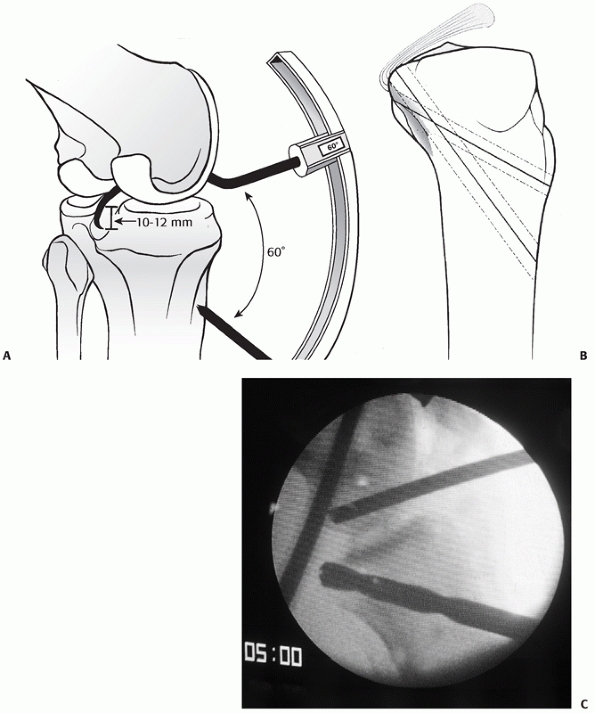

an arthroscopic ACL/PCL reconstruction using the transtibial technique

Two of the authors prefer a tibial inlay for the PCL (Fig. 54-19), while one prefers the transtibial technique (Fig. 54-20).

![]() |

FIGURE 54-19 A. Drawing and B,C. radiographs of a tibial inlay posterior cruciate ligament reconstruction.

FIGURE 54-20 A. The transtibial arthroscopic tunnel created for posterior cruciate ligament reconstruction. B.

Creating the tunnel properly necessitates a posterior and relatively distal position on the tibia to recreate the posterior cruciate ligament (PCL) insertion site. C. This lateral radiograph of a failed PCL reconstruction using a transtibial tunnel approach shows the tunnel was placed too anteriorly. A,B. redrawn from and C from Scott WN, Insall JN. Video textbook. Philadelphia: JB Lippincott, with permission.) |